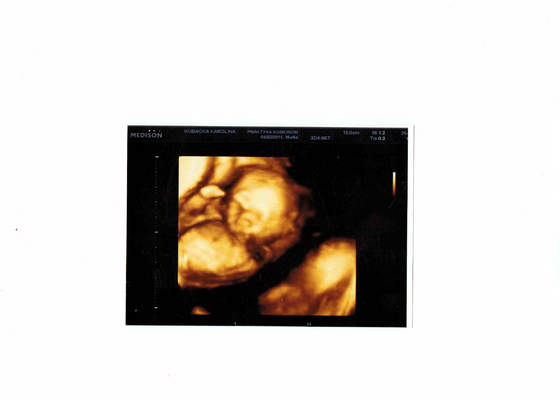

Moje przeczucia się sprawdziły będziemy mieli synka:) Widziałam siusiaka i jajeczka na usg.Mały pięknie rośnie ma 12,5cm i waży 210 gram,to więcej niż powinien:)

Podczas badania machał rączkami i ssał kciuka że trudno było mu zrobić zdjęcia nie zasłaniając bużki.Jestem taka szczęśliwa:)

A to fotka mojego kochanego synka 16 tydz i 6 dzień.